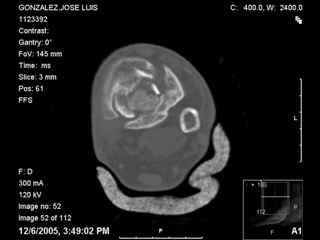

A 56 year old laborer fell off a wall approximately 5 months ago. He sustained an open pilon fracture. He was treated with debridement and external fixation. After he was treated for 4 months, the external fixator was removed.

I have attached his x-rays. I have also attached an WMV movie file of his axial CT (if you are unable to view this, I can post an MPEG file).

It seems to be a definite nonunion from the plain XRs.

The subtalar joint looks okay from what we can see on the lateral x-ray so I wouldn't want to damage it if it can be avoided. If thorough workup (WBC, ESR, CRP) shows no evidence for infection, he's a nonsmoker (or has quit) and there's no sign of infection at surgery, I would try a "moderately invasive" ORIF with debridement and autologous bone grafting. I think with a precontoured plate with locking screw capability one could get adequate fixation distally to allow immediate ROM and provide compression across the fracture.